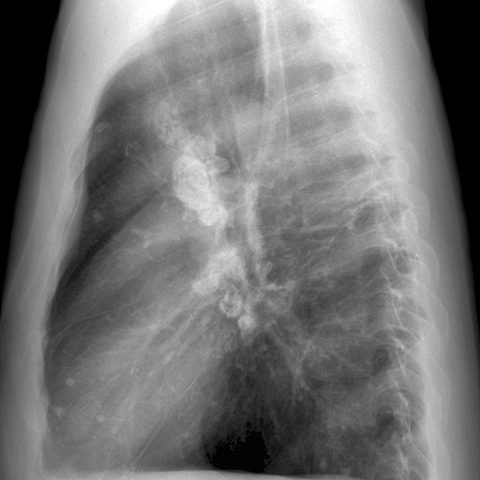

Calcified Hilar Nodes, Remote Granulomatous Infection [2 of 4]